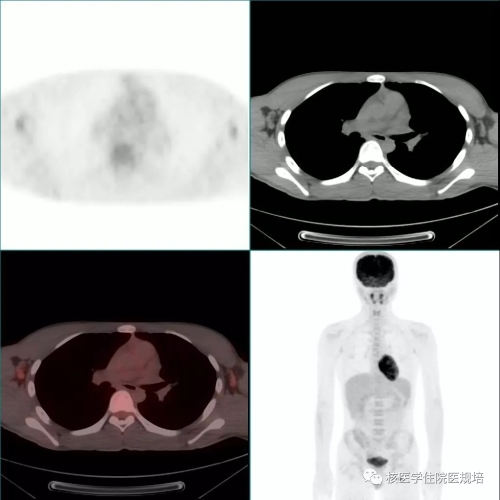

患者男性,20岁,2月前因发热待查就诊,影像学检查发现心脏占位。心脏超声示:左室前侧壁占位,彩色多普勒血流成像可见肿物血供丰富(图1);心脏MR示:左室中段及心尖段前侧壁占位,累及前组乳头肌,前侧壁可见粗大肿瘤血管(图2)。为明确左心室病变性质,行18F-FDG PET/CT显像(图3)。

图3

18F-FDG PET/CT显像见:左室前侧壁显影形态失常,MR所示占位相应部位与周围正常心肌组织对比呈不均匀FDG摄取减低区(SUVmax6.4),但肿物边界观察不清,相当于乳头肌处见点状FDG高摄取(图4);双侧腋窝区域分别可见一FDG摄取轻度增高(SUVmax1.8)的小淋巴结,对称性分布,淋巴结均呈长椭圆形,短径均小于1.0cm,内可见脂肪密度的门样结构(图5);另于左侧臀部下方皮下脂肪层内可见一点状FDG摄取增高灶(SUVmax6.1),相应部位CT见一边界较清晰的软组织密度结节影(图6,追问病史该结节已存在3年,局部无红肿热痛,大小始终无著变。全身其余部位未见明显异常结构改变及FDG摄取。